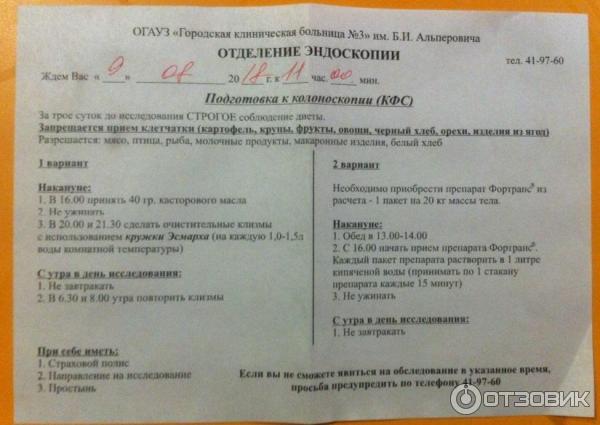

Подготовка к ирригоскопии: необходимые препараты